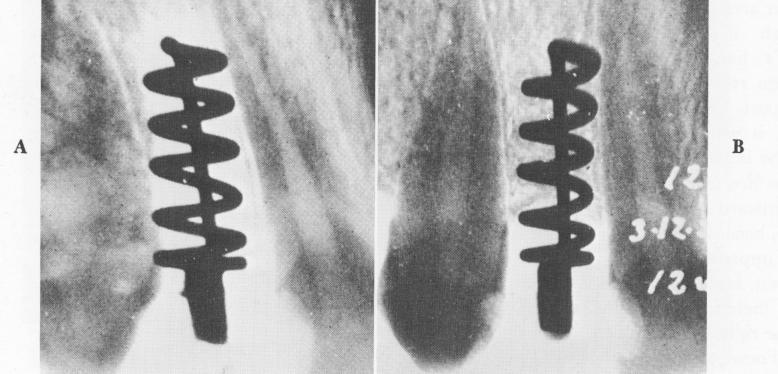

Perron-Andres experienced partial success with his all-metal implant (Fig. 5-32). However, as can be clearly seen in the x-rays, the design of his implant permitted the invagination of soft tissues around the first few spires. Following Formiggini's concept that it was the number of spirals, not the

Fig. 5-32. A, A partially successful Perron-Andres implant just after insertion. B, Bone has clearly grown around and through most of the spirals. However, the superficial spires are surrounded by soft tissues. (From Chercheve, R.: Les implants endo-osseoux, Paris, 1962, Librairie Maloine.)